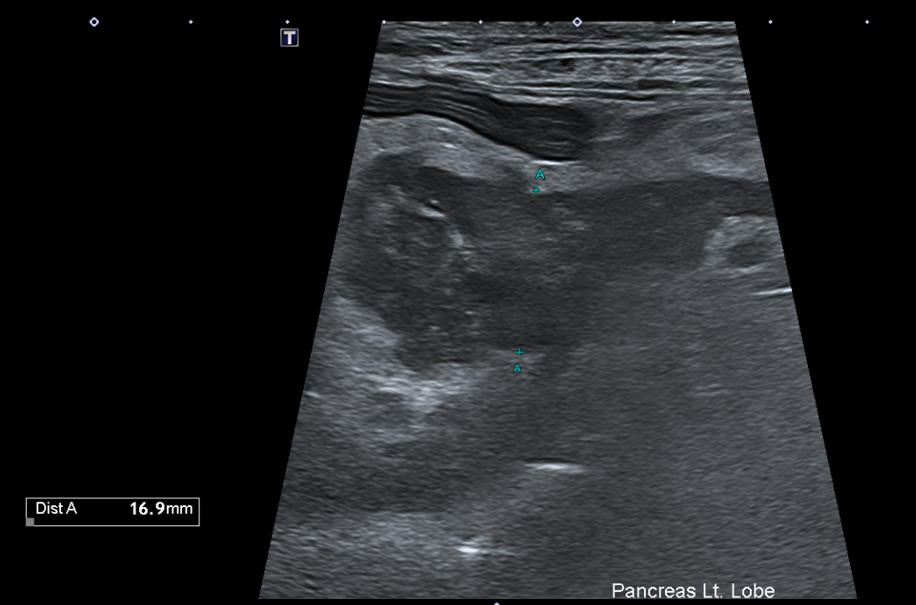

복부초음파

또한 복부 초음파상에서 뚜렷한 췌장 비후, 저에코성 음영, 주변 복막의 고에코성 소견 -> 확인되어 췌장염이 강력 의심되는 상황이었습니다.

Figure 2. 췌장 비후와 주변 복수 확인됨.

환자의 경우 뚜렷한 소화기 증상, 뚜렷한 염증 소견과 QPL 수치 상승, 복부초음파상 췌장염 비후, 복수 소견 확인되어 췌장염으로 진단되었습니다.